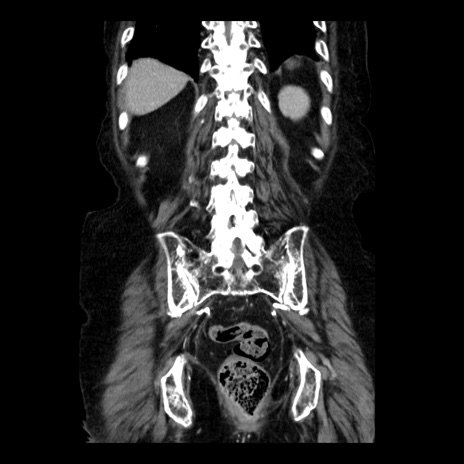

症例14(冠状断像)

【症例】 90歳代女性

【主訴】 腹痛・嘔吐

【現病歴】今朝から左側腹部痛を認めた。 経過観察していたが、嘔吐を認めたため来院。

【既往歴】 子宮癌術後

【身体所見】 意識清明、BP 127/54mmHg、P 98bpm Sp02 95%(RA)、BT 35.8°C、腹部平坦・軟腸ぜん動音聴取良好、右下腹部圧痛(+) 反跳痛なし

【データ】WBC 9800、CRP 0.46